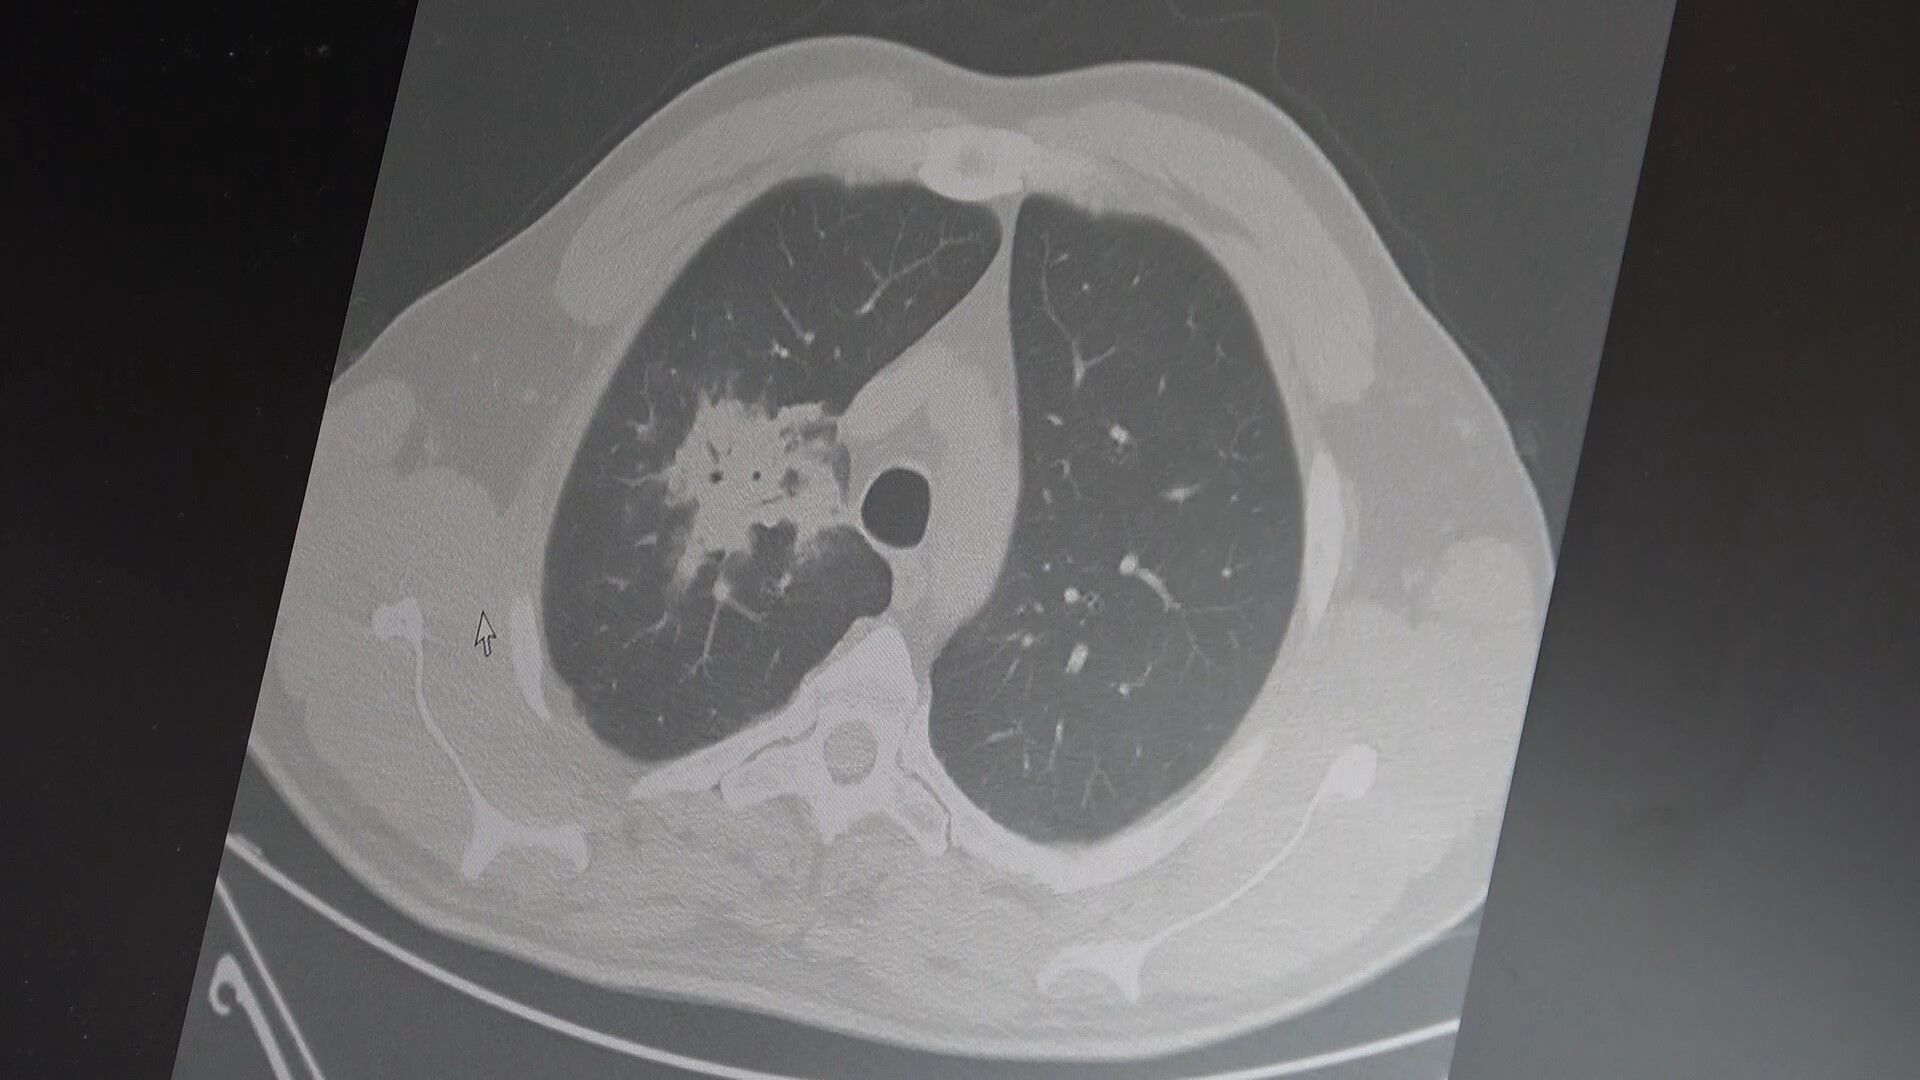

Elektronik sigaraların 2000'li yılların başında geleneksel sigaraya göre daha temiz, daha az kokulu ve daha güvenli bir alternatif olarak pazarlandığını hatırlatan Prof. Dr. Özkaya, milyonlarca kişi tarafından hızla benimsendiğini söyledi. Kullanıcıların yıllardır "Zararı var mı, sigaraya göre daha mı zararsız" sorusunu yönelttiğini ifade eden Özkaya, "Biz her zaman bu tür ürünlerin zararlarının en az 20-30 yıllık kullanım sonrası ortaya çıkacağını söyledik. Bu süre doldu ve bilimsel veriler gelmeye başladı" diye konuştu. 100'den fazla bilimsel çalışmanın incelendiği kapsamlı analizlere dikkat çeken Özkaya, elektronik sigaraların özellikle temas ettiği akciğer ve ağız bölgelerinde kanser riskini artırabileceğine dair güçlü bulgular bulunduğunu belirtti. Uzun vadeli sonuçların henüz tam olarak ortaya çıkmadığını ancak erken uyarı işaretlerinin ciddi olduğunu vurguladı. Araştırmalarda insan, hayvan ve laboratuvar verilerinin birlikte değerlendirildiğini aktaran Özkaya, elektronik sigaraların içerdiği kimyasalların hücre düzeyinde zarara yol açtığının ortaya konulduğunu ifade etti. Elektronik sigaraların DNA hasarı, oksidatif stres ve kronik iltihaplanma gibi kanser gelişiminde kritik rol oynayan üç temel mekanizmayı tetiklediğini belirten Özkaya, "Bu üç faktörün doğrudan kanser oluşumuna neden olduğunu biliyoruz" şeklinde konuştu.

2024 yılında yayımlanan bir çalışmaya da değinen Özkaya, hem geleneksel sigara hem de elektronik sigara kullanan bireylerde akciğer kanseri riskinin, sadece sigara içenlere göre dört kat daha fazla olduğunun bildirildiğini kaydetti. Elektronik sigara kullanımının özellikle gençler arasında yaygınlaştığını ifade eden Özkaya, lise çağındaki bireyler ve 40 yaş altındaki kişilerde kullanım oranlarının arttığına dikkat çekti. Elektronik sigara ile başlayan gençlerin ilerleyen süreçte normal sigaraya geçiş yapma ihtimalinin daha yüksek olduğunu belirtti. Özkaya, erken bilimsel bulguların göz ardı edilmemesi gerektiğini vurgulayarak, "Bugün gerekli önlemler alınmazsa, gelecekte çok daha büyük bir halk sağlığı sorunu ile karşı karşıya kalabiliriz" ifadelerini kullandı.